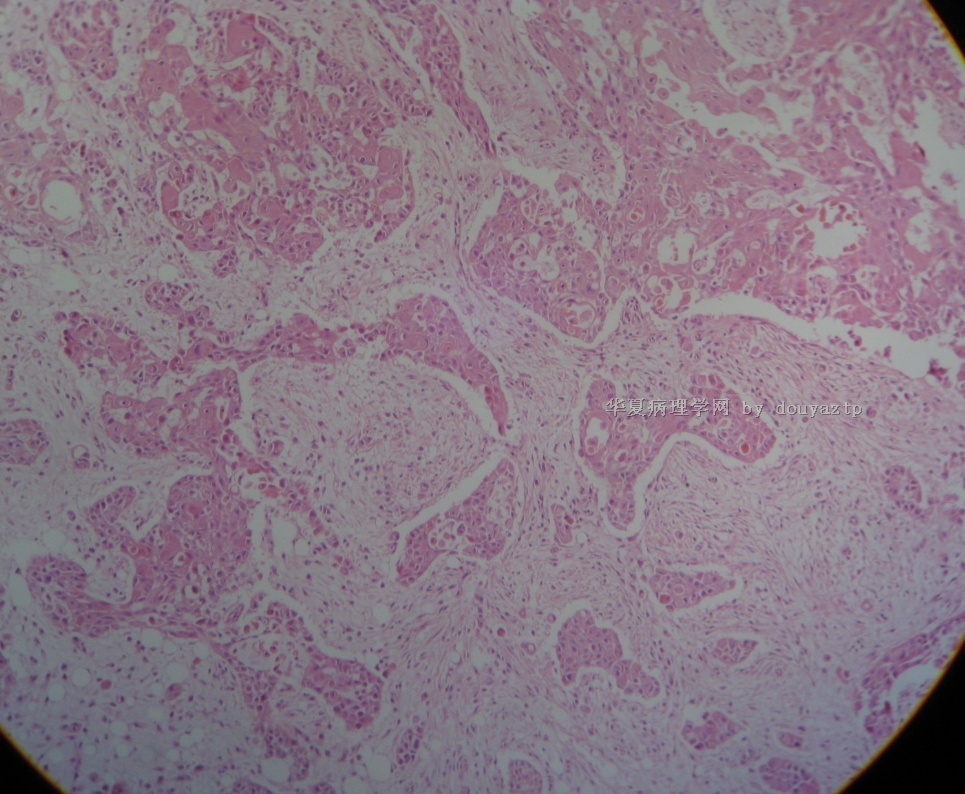

男性,37岁,大量血性胸水

这是几天后送检的病人右上腹壁的皮下包块。